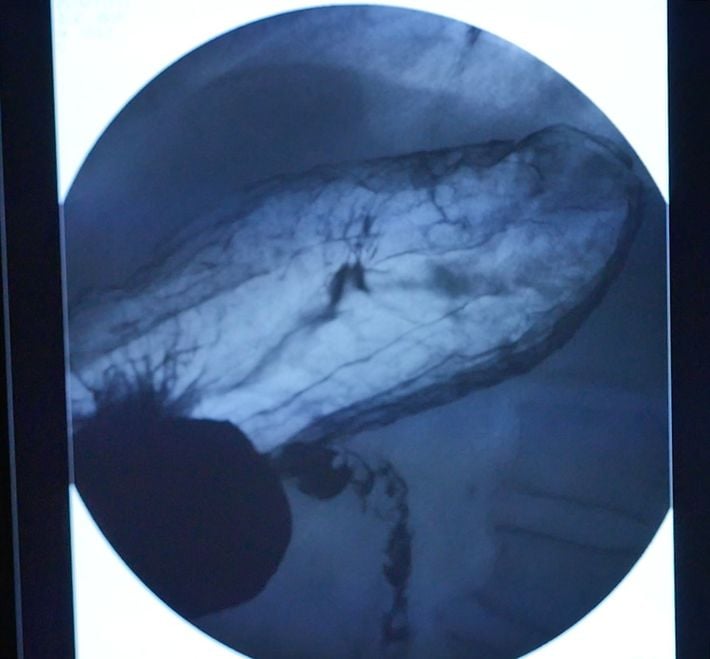

バリウム検査では、早期がんの発見が難しい

検査で飲用するバリウム液の「誤嚥事故」も少なくない

切り取られた胃がんの病巣

超音波内視鏡(EUS)検査の様子